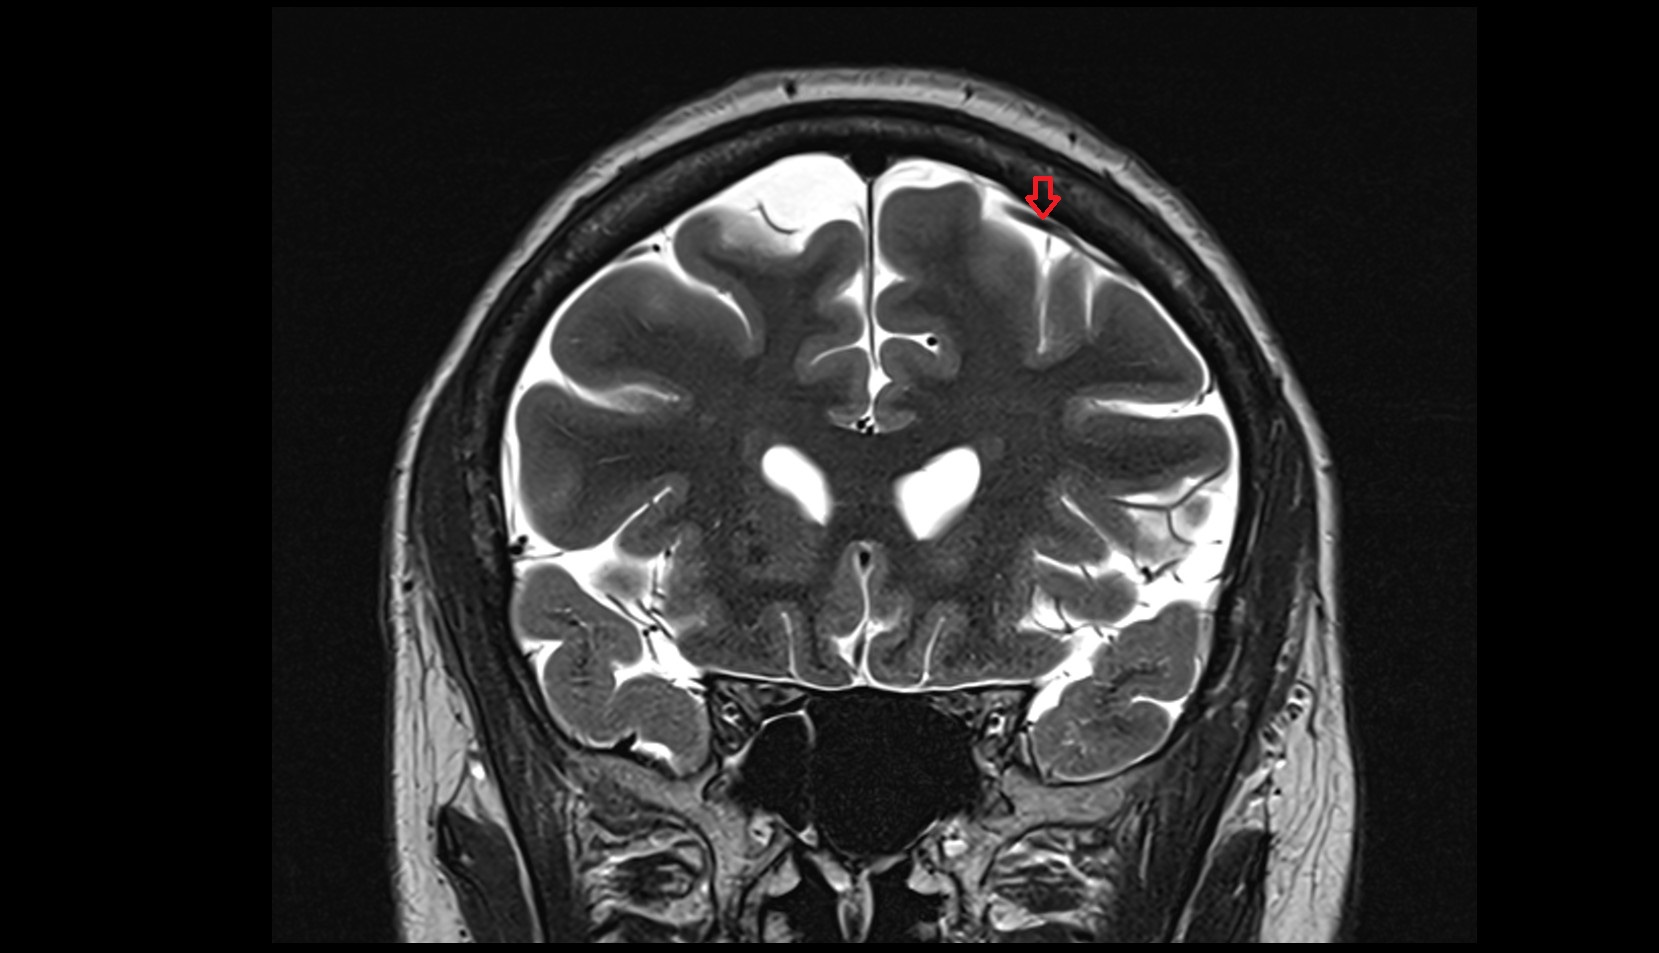

- Superficial cerebral veins

- Superior anastomotic vein

- Superior sagittal sinus

- Superior cortical veins